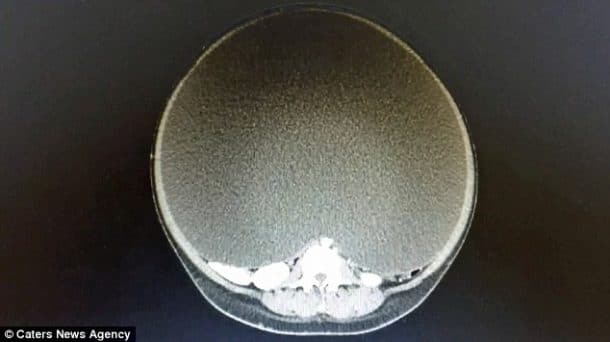

Les médecins lui ont donc fait passer des tonnes d’examen et c’est après une énième échographie qu’ils ont découvert ce qu’elle avait. En effet, ce que vous voyez là n’est autre qu’un kyste à l’ovaire. Un kyste extraordinairement gros. Ce kyste pesait 33kg. Deux options s’offraient à la patiente : tenter de vider le kyste ou opter pour une opération afin de l’enlever complètement.